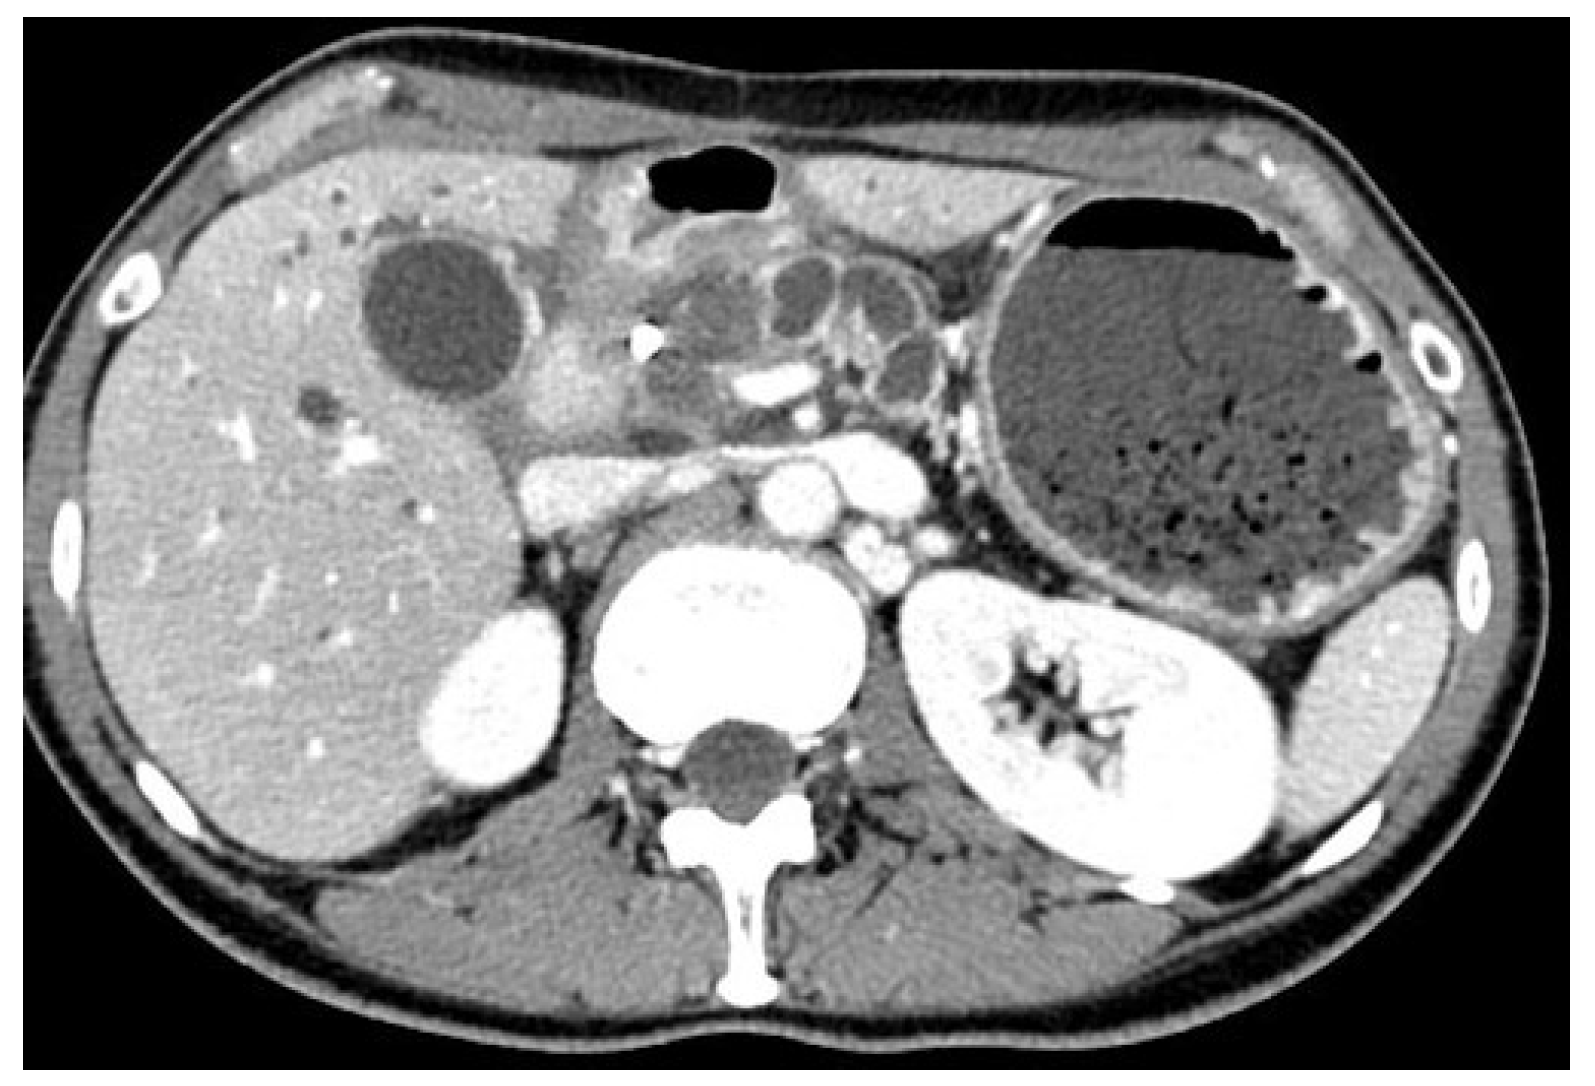

5.1. Direct Unassisted EUS-GE

5.2. Device-Assisted EUS-GE